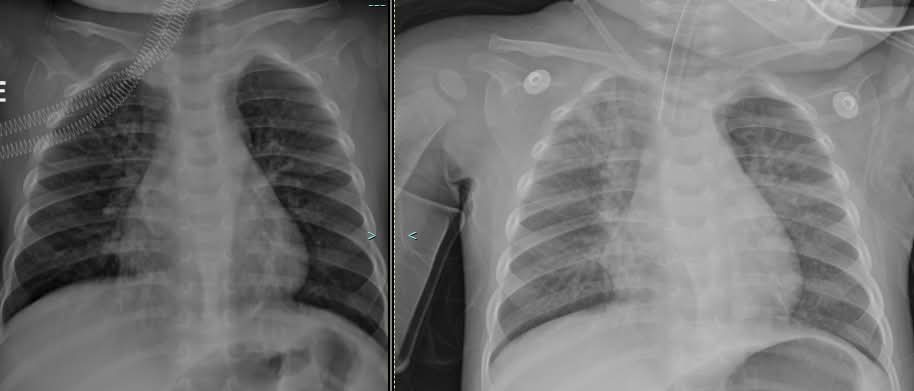

ภาพเอกซ์เรย เปลี่ยนไปอย่างรวดเร็ว แม้ผลการตรวจอื่นๆ

จะไม่ได้ชี้ว่า มีการติดเชื้อแบคทีเรียซ้ำซ้อนด้วยหรือไม่